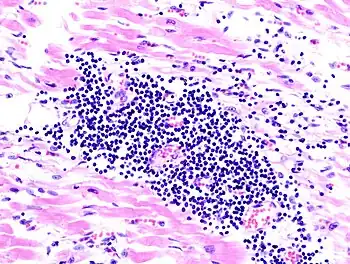

Most forms of myocarditis involve the infiltration of heart tissues by one or two types of pro-inflammatory blood cells, lymphocytes and macrophages plus two respective descendants of these cells, NK cells and macrophages. Eosinophilic myocarditis is a subtype of myocarditis in which cardiac tissue is infiltrated by another type of pro-inflammatory blood cell, the eosinophil. Eosinophilic myocarditis is further distinguished from non-eosinophilic myocarditis by having a different set of causes and recommended treatments.[34][18]

The gold standard is the biopsy of the myocardium, in general done in the setting of angiography. A small tissue sample of the endocardium and myocardium is taken and investigated. The cause of the myocarditis can be only identified by a biopsy. Endomyocardial biopsy samples are assessed for histopathology (how the tissue looks like under the microscope): myocardial interstitium may show abundant edema and inflammatory infiltrate, rich in lymphocytes and macrophages. Focal destruction of myocytes explains the myocardial pump failure.[10] In addition samples may be assessed with immunohistochemistry to determine which types of immune cells are involved in the reaction and how they are distributed. Furthermore, PCR and/or RT-PCR may be performed to identify particular viruses. Finally, further diagnostic methods like microRNA assays and gene-expression profile may be performed.